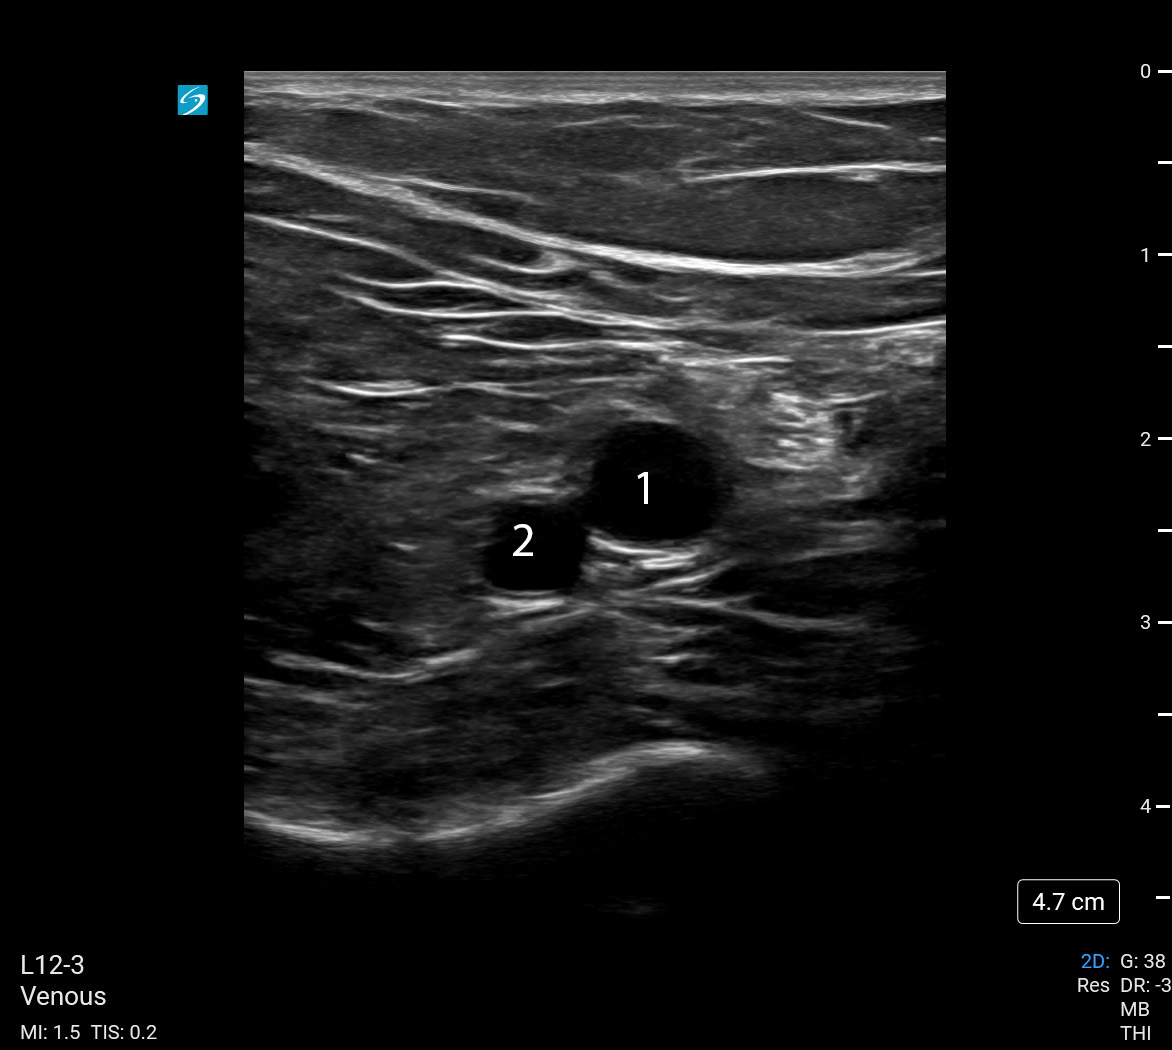

Deep Vein Thrombosis (DVT) Popliteal Vein and Artery Image

Popliteal Vein

Popliteal Artery